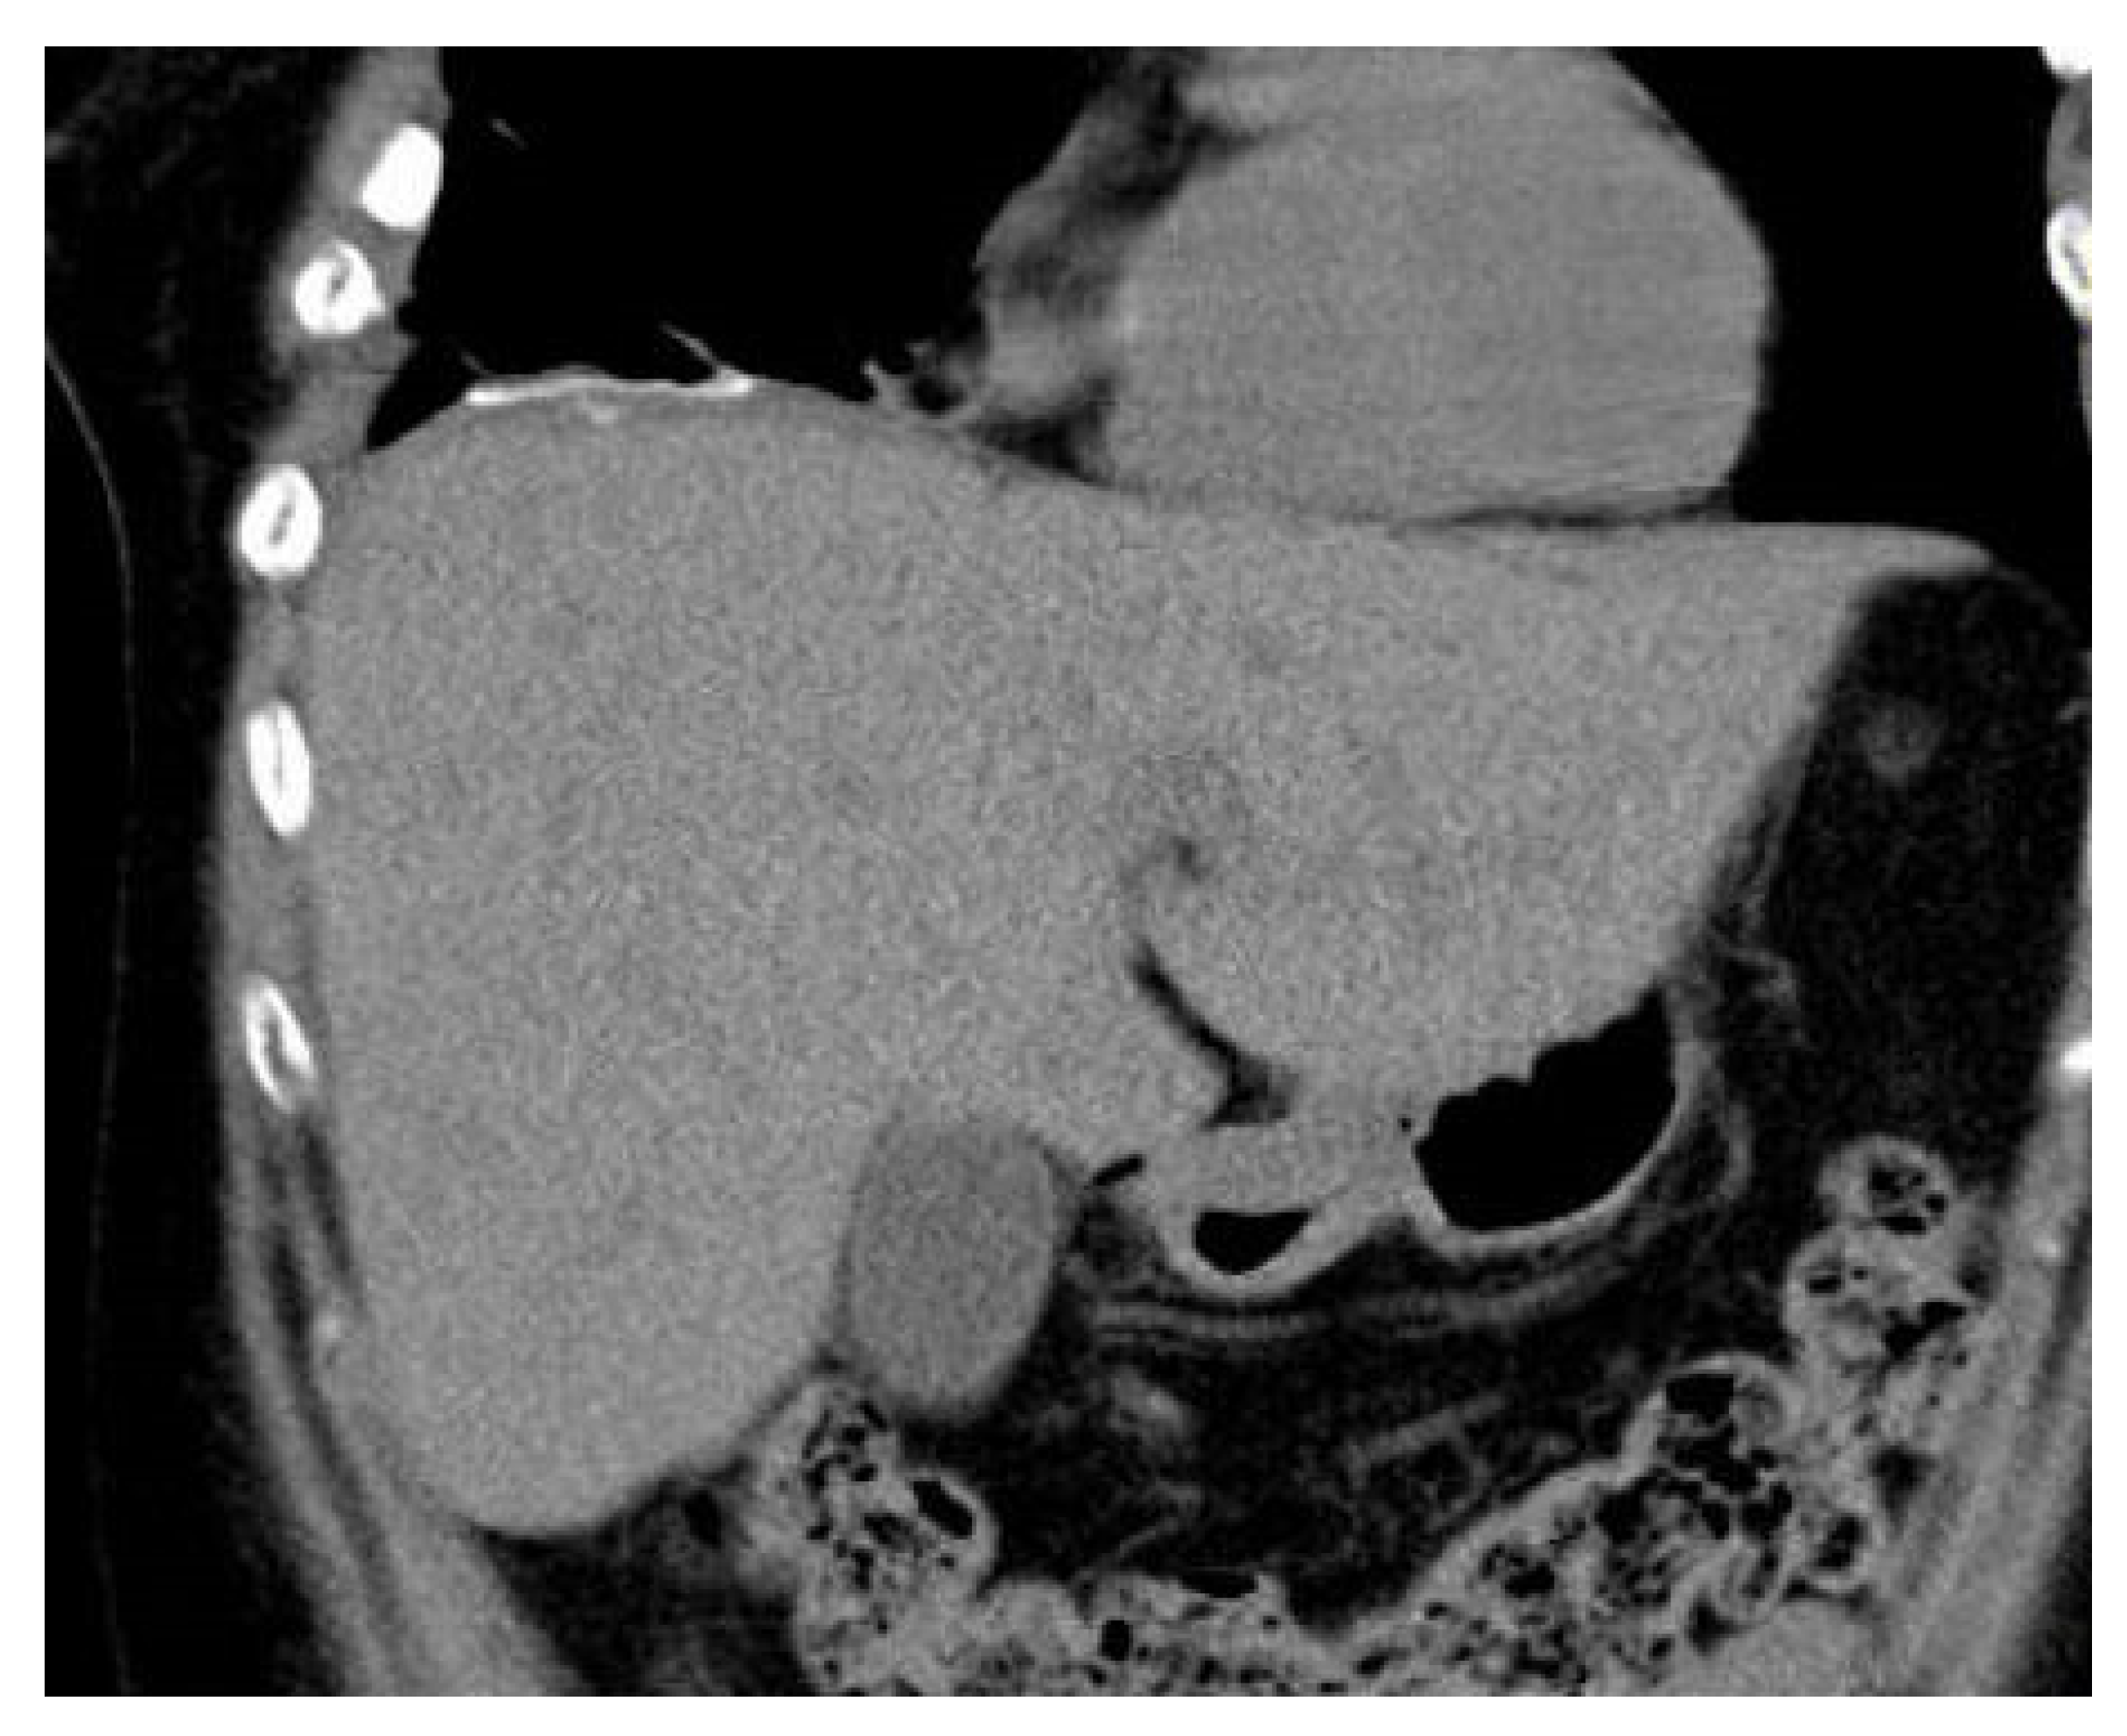

Diaphragmatic Liver Herniation after Radiofrequency Ablation of a Secondary Liver Tumor